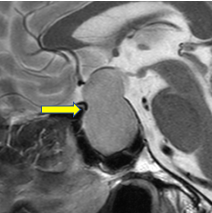

年末から軽い左後頭部痛があり、年初に目の前が白くなる症状があったそうです。起床時から物が二重に見えるようになり、瞼が塞がってきたために来院されました。

左第三脳神経(動眼神経)麻痺がみられました。左内頚動脈の脳動脈瘤が大きくなり、第三脳神経を圧迫したためにおこったものです。くも膜下出血が迫っている兆候ですので急遽手術となりました。

脳動脈瘤をクリップで処理しました。